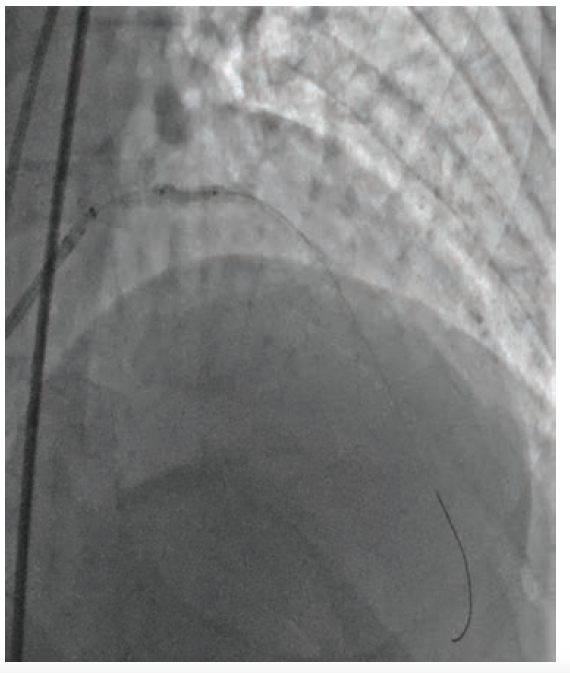

The patient is a 77-year-old male with a history of hypertension and hyperlipidemia who presented to our group at Cardiovascular Specialists of New England (CSNE) after a cardiac catheterization showed a chronic total occlusion of the proximal left anterior descending (LAD) coronary artery (Figure 1). A cardiac stress PET showed a large reversible defect in the anterior and anterolateral walls of the left ventricle. He continued to have exertional angina despite maximum medical therapy. We performed a repeat angiogram with dual injections from the right coronary artery and left main. After successful traversal of the chronic total occlusion of the LAD using a Turnpike Spiral microcatheter (Teleflex) and .014-inch Mongo wire (Asahi Intecc), 2.5 mm and 3.0 mm noncompliant balloons were unable to expand the lesion (Figure 2).